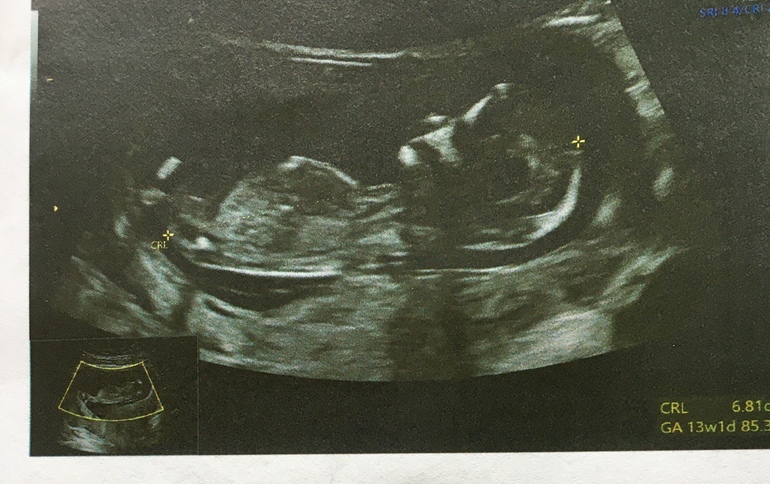

Сделали узи, малыш растёт, ктр 6.8 см, немного опережает срок, чсс 149/мин, толщина воротниковой складки 1,8, носовая косточка есть) Помахал нам ручками, вёл себя очень активно.